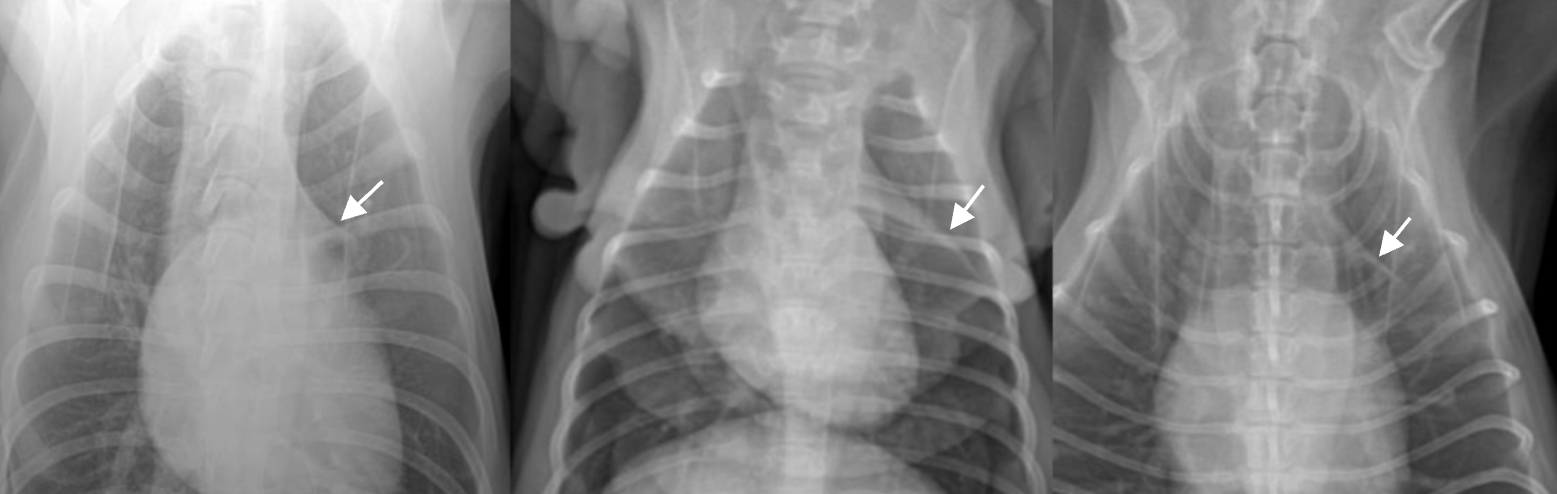

Thymus (sail sign)![]() - ์ด๋ฆฐ ๋๋ฌผ์์ thymus๊ฐ ๋จ์์๋ ๋ชจ์์ โsail signโ์ด๋ผ๊ณ ํจ. (๋ชจ์์ ๋ค์) |

| Skin fold - ๊ธฐํ๊ณผ ํท๊ฐ๋ฆฌ๊ฒ ์๊ฒผ์ง๋ง, ์์ธํ ๋ณด๋ฉด ๋ฐ๊นฅ์ด๋ ์ด์ด์ง๊ณ ์์. |

CCJ (costso-chondral junction) ![]() - ํ๊ฒฐ์ ๊ณผ ์ค์ธํ์ง ์๋๋ก. - ๋ฅ์คํํธ์์๋ ๊บพ์ด์ ๊ด์ ํ๊ธฐ ๋๋ฌธ์ ๋ ๋๋๋ฌ์ง. |

| Retrosternal fat accumulation : ์ฌ์ฅ ๊ทผ์ฒ์ ์ง๋ฐฉ์ด ์ฐฐ ์ ์๋ค. |

Pulmonary osseus metaplasia : ํ์ ์ํํ (๋

ธ๋ น์ฑ)![]() (ํ์ ์ด์ ๋นํด ๋๋ฌด ์๊ณ , opacity๊ฐ bone์ ๋ ๊ฐ๊น์) |

Knob sign ![]() - ๋์ด ๋ง์ ๊ณ ์์ด์์ ๋๋๋งฅ์ด ๊ตฌ๋ถํด์ง๊ณ , ์ฌ์ฅ์ด ๋์. |